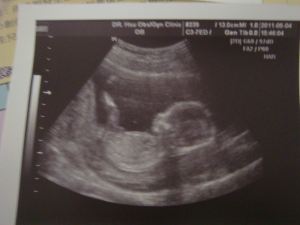

呵呵,恭喜小路,baby 看起來鼻子很挺呢!謝謝小提琴 !! 女婿也這麼說。

這兩天在替她買些孕婦裝,再過來得逛逛 baby sections 了。 Really a new adventure.... 恩典小路 於 2011/05/21 11:05回覆 - 7樓. LJ2011/05/19 18:05很少看到這麼清楚的超音波照片!